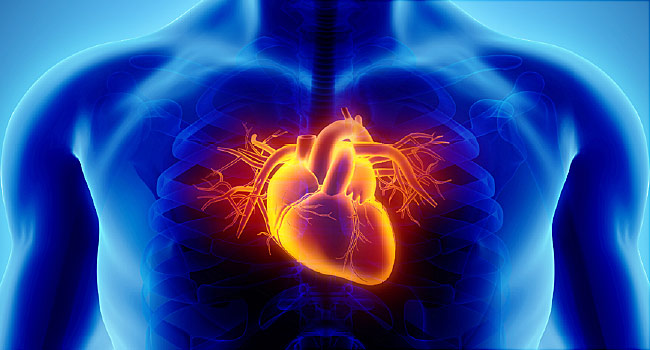

Nutritious diet is very important to keep the heart healthy. If you have heart-related problems, then you should use such things in food, so that your heart remains healthy and strong.

Along with this, you should immediately remove the things from your diet that can cause harm to the heart. One should say no to smoking, outside packed food, more oily, soda cold drinks and alcohol from life.

To stay healthy, it is very important for you to control your weight. Today we are telling you such dangerous things for a healthy heart, which you should stop consuming from today itself.

Below listed are a few foods you should keep distance from: